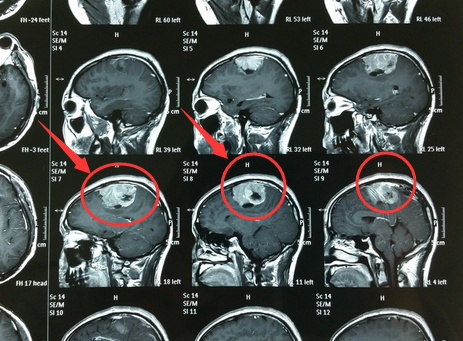

左顶镰旁脑膜瘤,是指位于大脑左顶镰旁位置的脑膜瘤,脑膜瘤是常见的轴外原发脑瘤,占全部原发中枢神经系统(CNS)肿瘤的三分之一。库欣首先将脑膜瘤描述为一组由CNS硬脑膜覆盖层引起的肿瘤,可在任何发现硬脑膜的地方发生。

左顶镰旁脑膜瘤手术未做干净怎么办?左顶镰旁脑膜瘤大多埋藏在大脑半球纵裂中,其位置较深,手术更难做干净了,那么,左顶镰旁脑膜瘤手术未做干净该怎么办呢?一般来说,脑膜瘤手术后就已经知道它的病理级别和类型了,这对于手后续处理至关重要。当然,还要结合残留的大小、病人的年龄、身体状况等多个因素来确定更佳的处理方案。